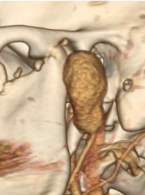

Ostra infekcja zębopochodna współistniejąca z chondrokalcynozą: opis przypadku

Zobacz więcej